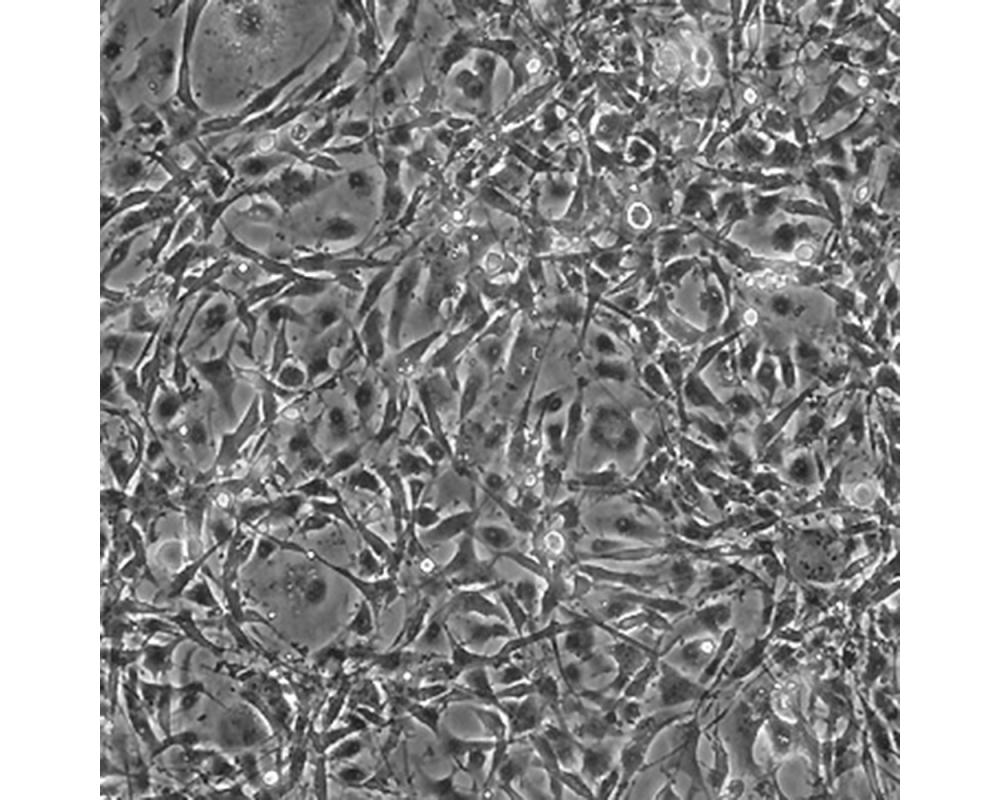

U-118 MG

中文名稱 人腦星形膠質(zhì)母細(xì)胞瘤

組織來源 星形膠質(zhì)母細(xì)胞瘤;男性

生長(zhǎng)特性 adherent

形態(tài)特征 mixed

細(xì)胞描述 注意: 據(jù)報(bào)道來自不同個(gè)體的膠質(zhì)母細(xì)胞瘤細(xì)胞株U-118 MG (HTB-15) 和 U-138 MG (HTB-16)有著一致的VNTR和相近的STR模式。 U-118 MG 和 U-138 MG細(xì)胞遺傳學(xué)上很相似并有至少六個(gè)衍生標(biāo)記染色體。 這是1966年至1969年間J. Ponten和同事從惡性神經(jīng)膠質(zhì)瘤中構(gòu)建的細(xì)胞株中的一株(其它包括ATCC HTB-14和 ATCC HTB-16 and ATCC HTB-17)。 1987年用BM-Cycline培養(yǎng)6周去除了支原體污染。